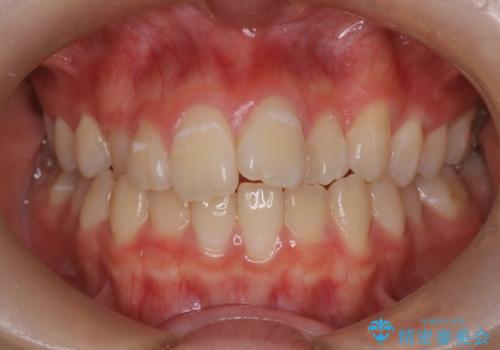

八重歯のワイヤーによる抜歯矯正 矯正治療と並行してセラミック治療も

ブリッジを装着している歯は動かすことができないので、矯正前に除去する必要があることがあります。

今回の場合も、ブリッジを除去して矯正後にセラミックブリッジを装着しました。